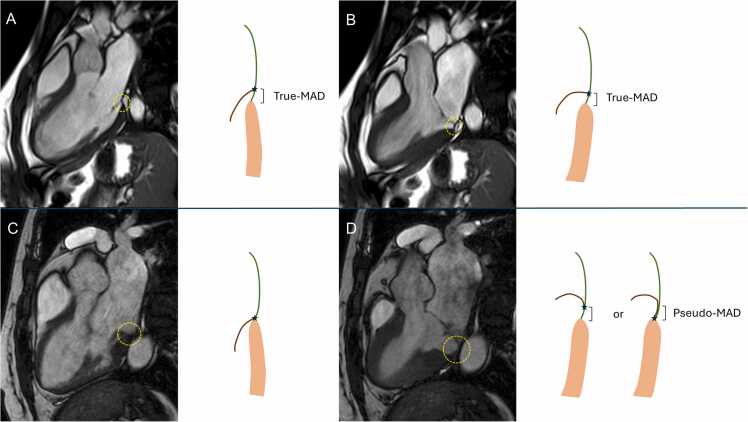

Background: Mitral annular disjunction (MAD) is a controversial entity. Recently, a distinction between pseudo-MAD, present in systole and secondary to juxtaposition of the billowing posterior leaflet on the left atrial wall, and true-MAD, where the insertion of the posterior leaflet is displaced on the atrial wall both in diastole or in systole, has been proposed. We investigated the prevalence of pseudo-MAD and true-MAD.

Methods: This was a retrospective study, including consecutive patients referred to cardiovascular magnetic resonance (CMR). MAD was defined as a ≥1 mm displacement between the left atrial wall-mitral valve leaflet junction hinge and the top of the left ventricular wall, measured from cine-CMR images in the three long-axis views. Pseudo-MAD and true-MAD were defined as the presence of MAD only in systole or both in systole and diastole, respectively.